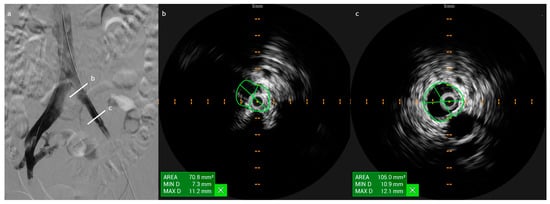

3. IVUS in Acute Lower Extremity DVT